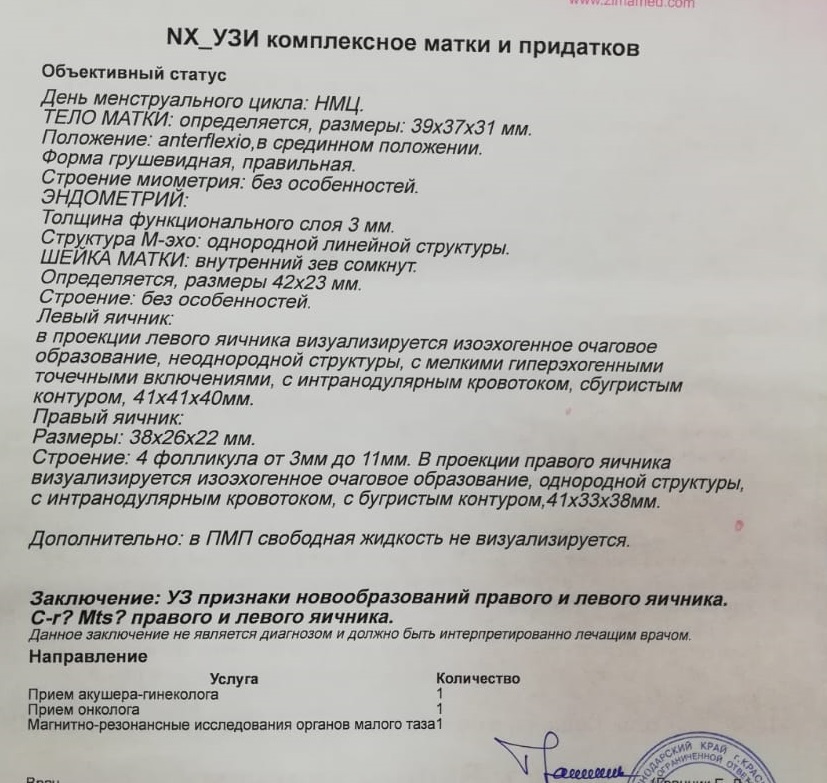

КТ-исследование абсцесса малого таза: Визуализация и диагностика

Раздел: Фотоальбом решений